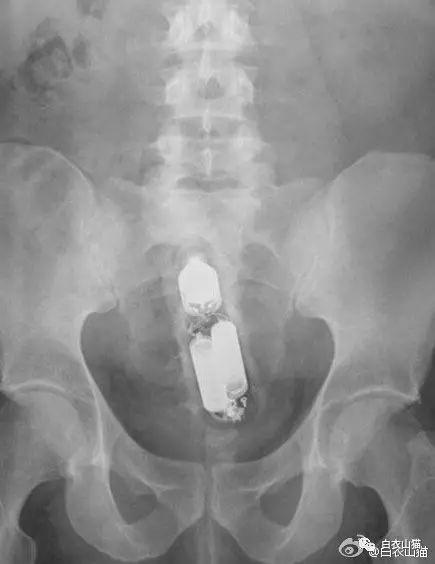

下面我们来看看常见的这些直肠异物。为了保护病人的隐私,X光片已经经过技术处理,看不出任何病人的信息。

大肠里的擀面杖。男性

这是做饺子皮用的擀面杖。对,全部塞进去了。你知道怎么看男女吗?看骨盆的角度。

取出的方法如同上面。